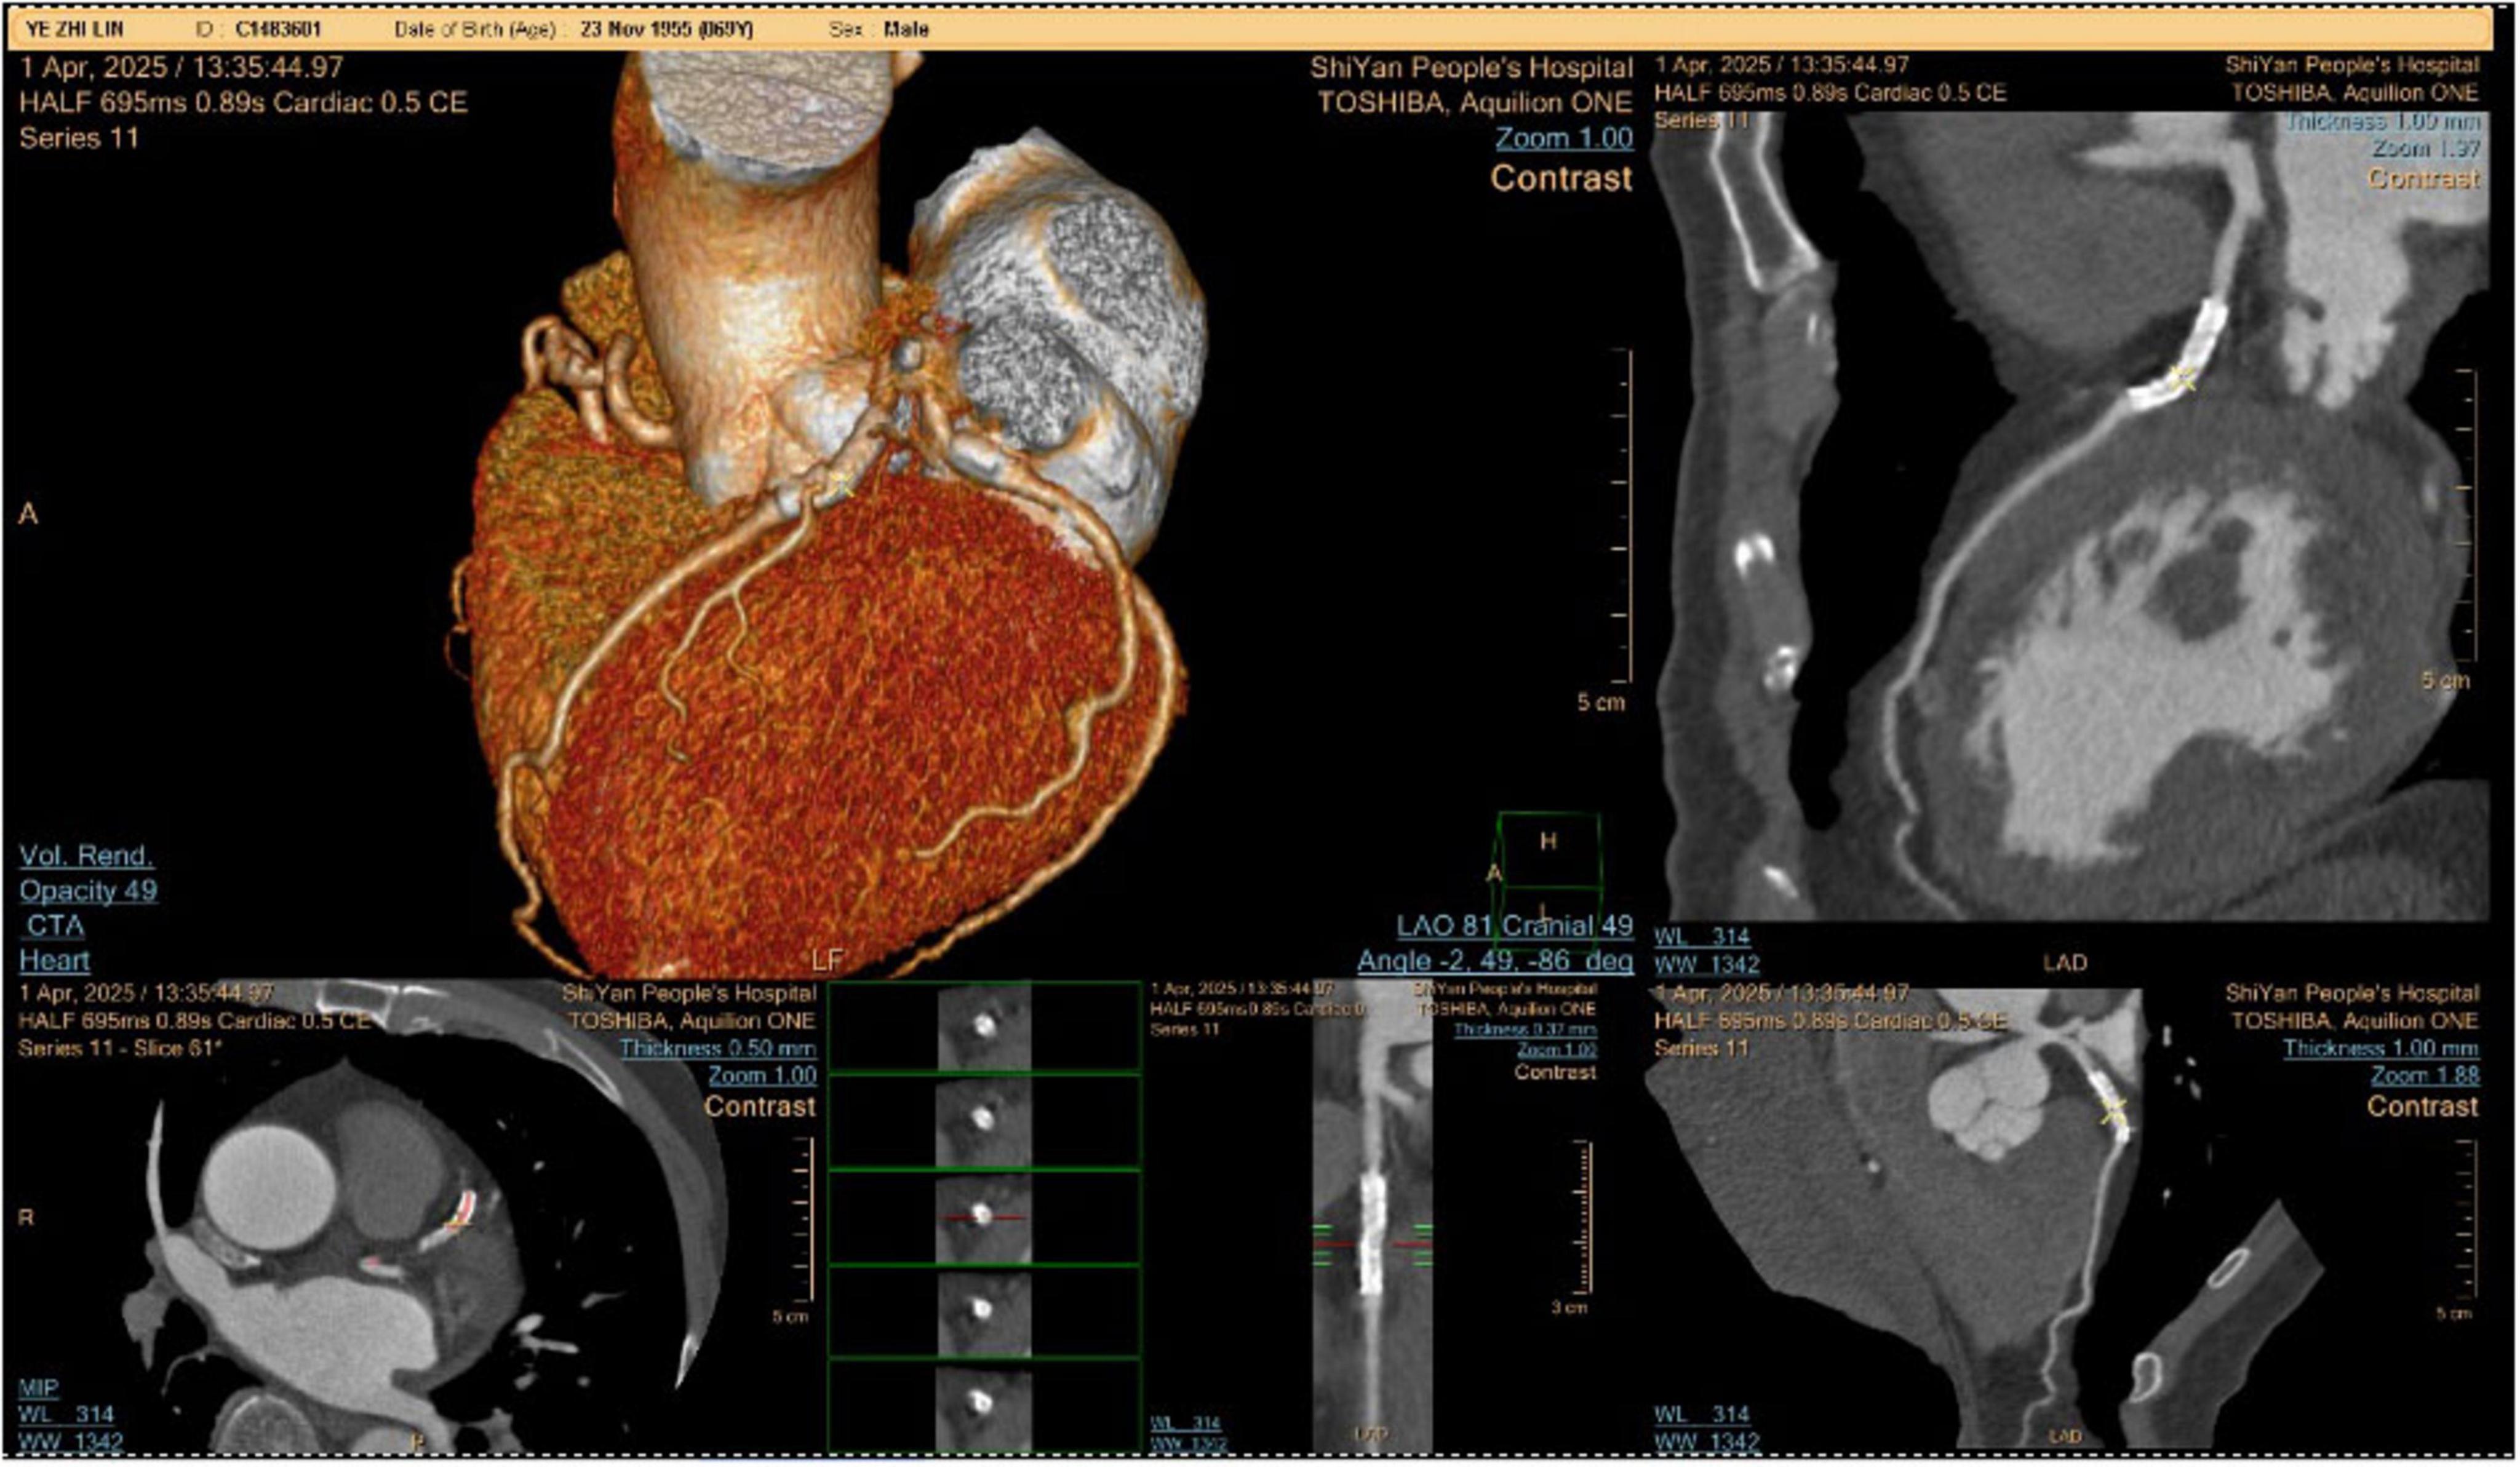

The patient was admitted to the hospital, and a cranial vascular CTA examination revealed cerebral atherosclerosis without obvious vessel stenosis (see Figure 1); a cranial MRI and DWI examination revealed bilateral cerebellar, bilateral frontal-parietal-temporo-occipital, and semiovoid central region infarcts (see Figure 2A); troponin levels were 0.224 ng/ml [ref (ref), 0.0–0.08 ng/ml], Creatine kinase isoenzyme 34 U/L [ref, 0.0–24 U/L], N-terminal brain natriuretic peptide precursor (BNP) 1324 pg/ml [ref, 0.0–300 pg/ml], and an electrocardiogram that suggested an ST-segment abnormality. Cardiovascular consultation was sought to rule out a non-ST-segment elevation myocardial infarction, and antiplatelet aggregation and lipid-modulating therapy were administered. The percentage of eosinophils was 43.4% [ref, 0.4%–8%], and tests for coagulation function, lipids, and liver and renal function revealed no appreciable abnormalities. Two days later, the patient developed severe precordial discomfort and dyspnea. Concurrently, limb muscle strength decreased significantly. On March 31, a physical examination revealed grade 3 muscle strength in the left upper limb, 0 in the right upper limb, and grade 2 muscle strength in both bottom limbs. Figure 3 depicts muscle strength scores provided by the Medical Research Council (MRC). Troponin, creatine kinase isoenzyme, and eosinophil percentage were all steadily declining compared to the prior time frame. As shown in Figure 3, the acidophilic fraction increased steadily. He was moved to the critical care unit (ICU) on March 31 in order to receive correctional treatment. According to a perfect coronary CTA examination, the coronary artery wall had many segmental mixed plaque formation, mild stenosis in the lumen, and an anterior descending branch of the middle section of the stent, which was about 2.3 cm long. The stent did not exhibit any visible fractures or restenosis symptoms, as shown in Figure 4. Bilateral cerebellum, bilateral frontal-parietal-temporo-occipital and semiovarian central area of several spots, and a tiny patchy DWI high signal, measuring between 2 and 18 mm (slightly larger in extent than the previous MR 2025.03.27), were all suggested by the review of the cranial MRI test (see Figure 2B). On April 1, tests revealed a considerably higher eosinophil level. Eosinophilia was discovered following a consultation with the hematology department. To decrease eosinophils, methylprednisolone sodium succinate was administered first, followed by clopidogrel to limit platelet aggregation and low molecular weight heparin for anticoagulation. A bone marrow aspiration was performed to assess flow cytometry, FISH, and fusion genes. Figure 5A shows the flow cytometry results for April 5: an elevated eosinophil percentage. According to the bone marrow aspiration report, there were more eosinophils in the bone marrow and peripheral blood images. Figure 5B shows an increase in eosinophils. Fusion gene screening revealed no results for PCM1:JAK2, ETV6:JAK2, FLT3, ETV6:ABL1, and BCR:JAK2. FISH probe analysis: FGFR1, PDGFRA, and PDGFRB: negative. Low molecular heparin anticoagulation, clopidogrel antiplatelet aggregation, and eosinophils were all reduced by methylprednisolone sodium succinate. Eosinophil counts in the patient progressively returned to normal. The patient’s limb muscle strength improved between 4 and 11; both upper and lower limb muscular strength were grade 3 and grade 4, respectively. He was sent to the rehabilitation department for therapy, and on April 28, he was released from the hospital on June 1. The outpatient follow-up assessment showed that the patient’s limb muscle strength had restored to normal.

FIGURE 4

Coronary CTA examination.

Evaluation was first directed toward atherosclerotic complications (“posterior circulation ischemia” and “NSTEMI”) due to our patient’s history of CAD and hypertension. Three results, however, contradicted this: Coronary CTA: Myocardial damage is not caused by plaque rupture, rather mild stenosis; Temporal correlation: eosinophil increase (peak 43.4%) was accompanied by rising troponin/CK-MB, not ECG/angiographic abnormalities; Neurological paradox: The stable MRI infarct burden was not matched by progressive quadriparesis. This emphasizes that even in cases of established CAD, HES can mimic acute coronary syndromes, making the eosinophil count a “vital sign” in thrombotic presentations. Despite thorough FISH/RT-PCR screening, the lack of *FIP1L1-PDGFRA*, PDGFRB, FGFR1, and JAK2 fusions indicates that this is either idiopathic or myeloproliferative HES. This has two meanings: Diagnostic difficulty: In molecular-negative HES, such severe presentations are uncommon.